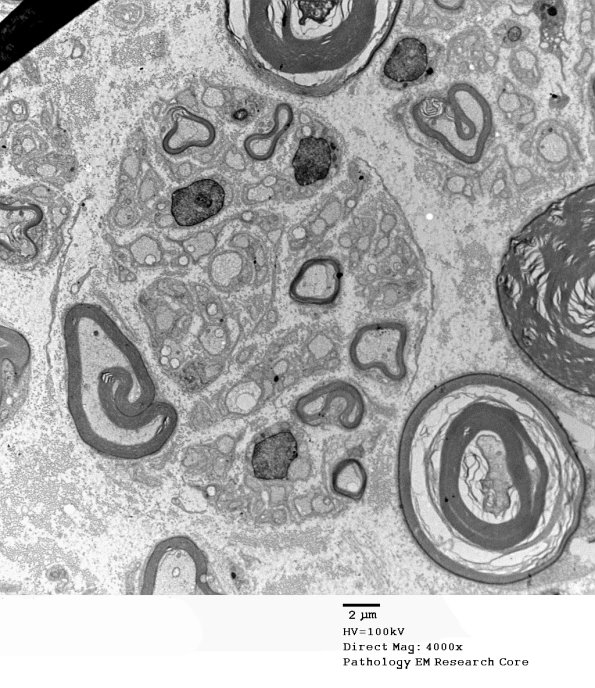

A number of examples of the aggregated small myelinated and unmyelinated axons which are not accompanied by significant loss of large myelinated axons. (Electron micrographs)